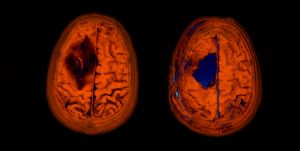

I believe there are around 4,000-5,000 images in total from 1 CT and 1 MRI scan! Thankfully there are tools that you can use to view these images. And not just view them, they allow you to navigate through all the scans. Each image is essentially a "slice" of the brain. The tools allow you to move through all 3 axis in near real time, with each of the corresponding panels changing depending on the input from the others.

It's so incredibly clever and absolutely fascinating (to me at least)! I spent the best part of 2-3 hours looking at my own brain scans. I wish I knew what it all meant, but I plan on quizzing the experts when I get the chance. I'd like to write a blog post all about it in the future. So, watch this space!

For those interested in doing the same the tools I used are:

Horos takes it a step further, as it allows you to view your scan in 3D, and even export an animation to show all your friends at the next soirΓ©e you attend! So yes, if you ever fancy looking at your own insides in detail, remember you can request your CT and MRI scan data!